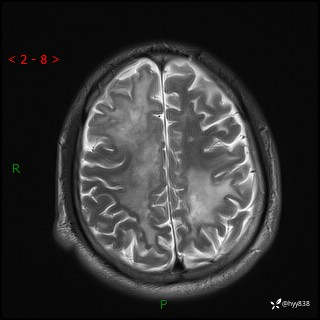

辅助检查:MRI

MRI T2WI